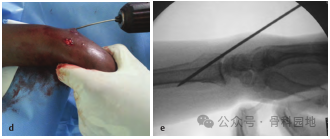

使用经典经皮克氏针固定桡骨远端骨折,如下图a-e 。

采用经皮克氏针固定后手指运动情况,如下图a-d 所示。